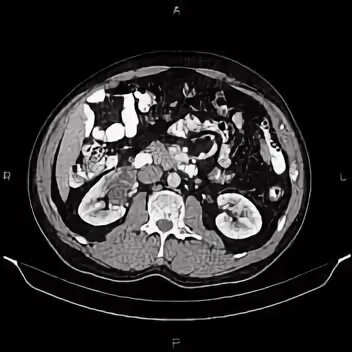

Ct search